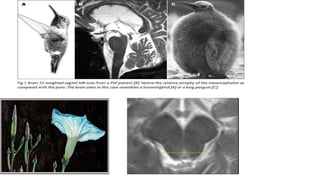

 MRI-

midbrain atrophy(appearance of a flat or concave profile -68% sensitivity and an 89%

specificity

Superior cerebellar peduncle atrophy.

“morning glory flower sign” and the “hummingbird sign” – Highly specific(100%) low

sensitivity (50% and 68.4%)

magnetic resonance parkinsonism index (MRPI) - sensitivity of 100%

and specificity of 99·2–100·0% for PSP-RS.

pons:midbrain ratio-